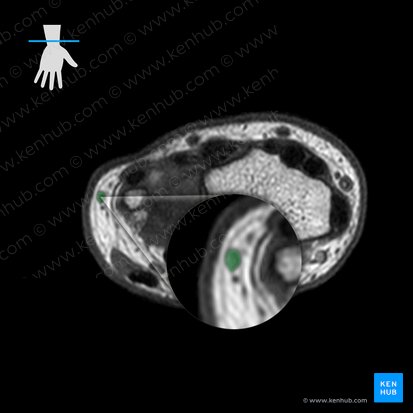

The orientation of the image remains identical to the previous axial section. However, only the radial styloid process is visible at this level on the right side. The ulna is no longer visible and has been replaced by other bones which will be described next. A new anatomical structure is now obvious, the carpal tunnel. It consists of many congregated hypointense ovals representing all the structures passing through it. The carpal tunnel can be used as the new inferior landmark instead of the previous dorsal radial tubercle, which is no longer visible superiorly.

Bones

We’ll follow a similar approach to the previous axial MRI to describe the visible structures. We’ll start with the skeletal framework i.e. the hyperintense bones. Quite a lot has changed at this level. Only the radial styloid process is visible on the extreme right hand side of the image and three carpal bones have become visible. Moving from right to left, you can see the scaphoid, lunate and triquetrum. If you know the anatomy of the proximal row of carpal bones, the order and location are quite obvious. The shape of the bones can guide you as well. The scaphoid resembles a boat, the lunate has a crescent (moon) shape and the triquetrum resembles a pyramid.

Ligaments

In contrast to the previous MRI image, there are several ligaments apparent in this axial view. You can see two thick, grey structures (intermediate intensity) spanning the superior and inferior margins of the radius, scaphoid and lunate bones. These are two extrinsic ligaments of the radiocarpal joint that connect the radius to each carpal bone; the dorsal and palmar radiocarpal ligaments. As their names imply, the dorsal radiocarpal ligament is located superiorly on the dorsal aspect. Its palmar counterpart is found inferiorly on the palmar aspect. Between the scaphoid and lunate bones you can see a thick, grey, interconnecting band. This is an intrinsic ligament of the radiocarpal joint which interconnects adjacent carpal bones. It is called the scapholunate interosseous ligament.

Continuing towards the left side (ulnar aspect), you can see two more grey thickenings overlying the lunate and triquetrum. These represent two extrinsic ligaments that connect the ulna to each carpal bone; the dorsal and palmar ulnocarpal ligaments. The former is located superiorly while the latter is inferior. It’s important to note that the radiocarpal and ulnocarpal ligaments are composed of several smaller ligaments, each named according to the carpal bone it connects to. However, they cannot be distinguished on this axial image. Last but not least, you can see the ulnar collateral ligament of the wrist joint on the far, extreme left. It connects the ulna to the triquetrum, so you can locate it very easily.